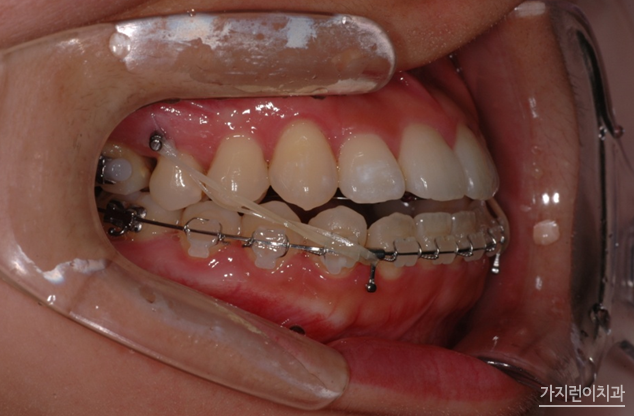

다음의 사진을 보면 미니스크류가 어떻게 이용되고 있는지 확인할 수 있는데요.

정말 작죠? 보시다시피 잇몸뼈나 입천장 등에 미니스크류를 심게 되는데요. 국소마취를 한 상태로 식립이 이루어지기 때문에 큰 통증은 없습니다. 하지만 마취가 풀리면 욱신거릴 수는 있어요. 꼭 필수는 아니지만 조금이라도 아픈 게 싫다?! 하는 분들이면 타이레놀 같은 진통제 복용이 도움이 됩니다. 또 나사를 뽑은 후에 잇몸에 구멍이 생기는 건 아니야? 하겠지만 공간이 작기 때문에 시간이 지나면 뼈와 살이 차오르게 됩니다. 걱정하지 않아도 된다는 소리죠-